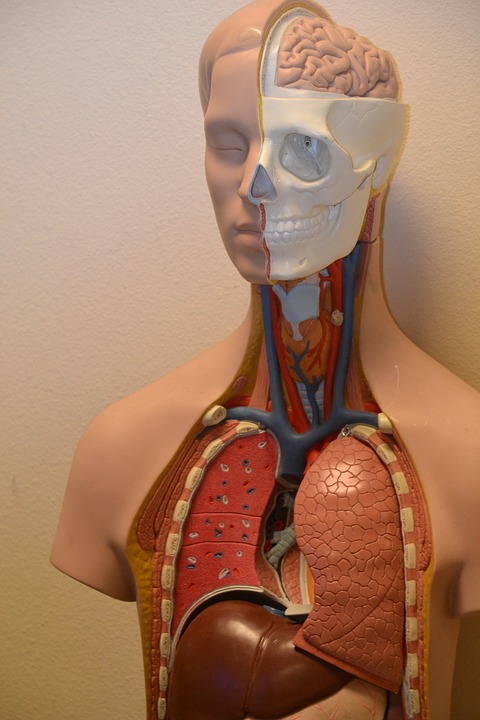

目前全世界只有伊朗是可以合法交易器官的國家,因此大家應該都有所耳聞在黑市中會有著非法器官買賣,只是你知道身體的器官到底價值多少錢嗎?或是你知道甚至連頭皮都有人收購嗎?美國網站《Ranker》就列出了在黑市中各個器官的價錢,還有最受歡迎的器官是哪個部位。

據悉在器官移植手術當中,大約有10%的器官或組織就是來自於黑市,但還是有50%的病患無法即時獲得他們所需的器官來進行移植。而在黑市中最受歡迎的,TEEPR吃不胖編相信大家應該多少有猜到,那就是「腎臟」,腎臟的價錢約是20萬美元 (約新台幣596萬元) 左右,在黑市中的交易比例高達75%,但是需要換腎的人很多,卻不是每個人都可以負擔;不過如果在中國或印度等地方價格就比較低,約是1.5萬至6.2萬美元 (約新台幣45萬至185萬元) ,但這也造成當地有不少偷腎賣腎的事件。

其他器官的價錢分別是:脾臟508美元 (約新台幣1.5萬元) 、眼角膜24.4萬元 (約新台幣727萬元) 、冠狀動脈1525美元 (約新台幣4.5萬元) 、骨髓每公克2.3萬美元 (約新台幣69萬元) 、血液每品脫337美元 (每473c.c.約新台幣1萬元) 。

除了上述所說的器官之外,其實在黑市中連頭皮和頭髮也是能交易的,黑市的眼光放得比較遠,他們認為未來醫術應該可以發展出透過頭皮移植來治療雄性禿的問題,因此已經開始囤積人類的頭皮,價格為600美元 (約新台幣1.8萬元) ;至於皮膚每10平方英吋10美元 (每65平方公分約新台幣298美元) 、頭髮每10英吋70美元 (每25公分約新台幣2084元) ,頭髮則是用來製作假髮後販賣。也因人體全身上下都很值錢,因此都有違法的器官切除和買賣在世界各個角落發生,隱藏著許多黑暗面。